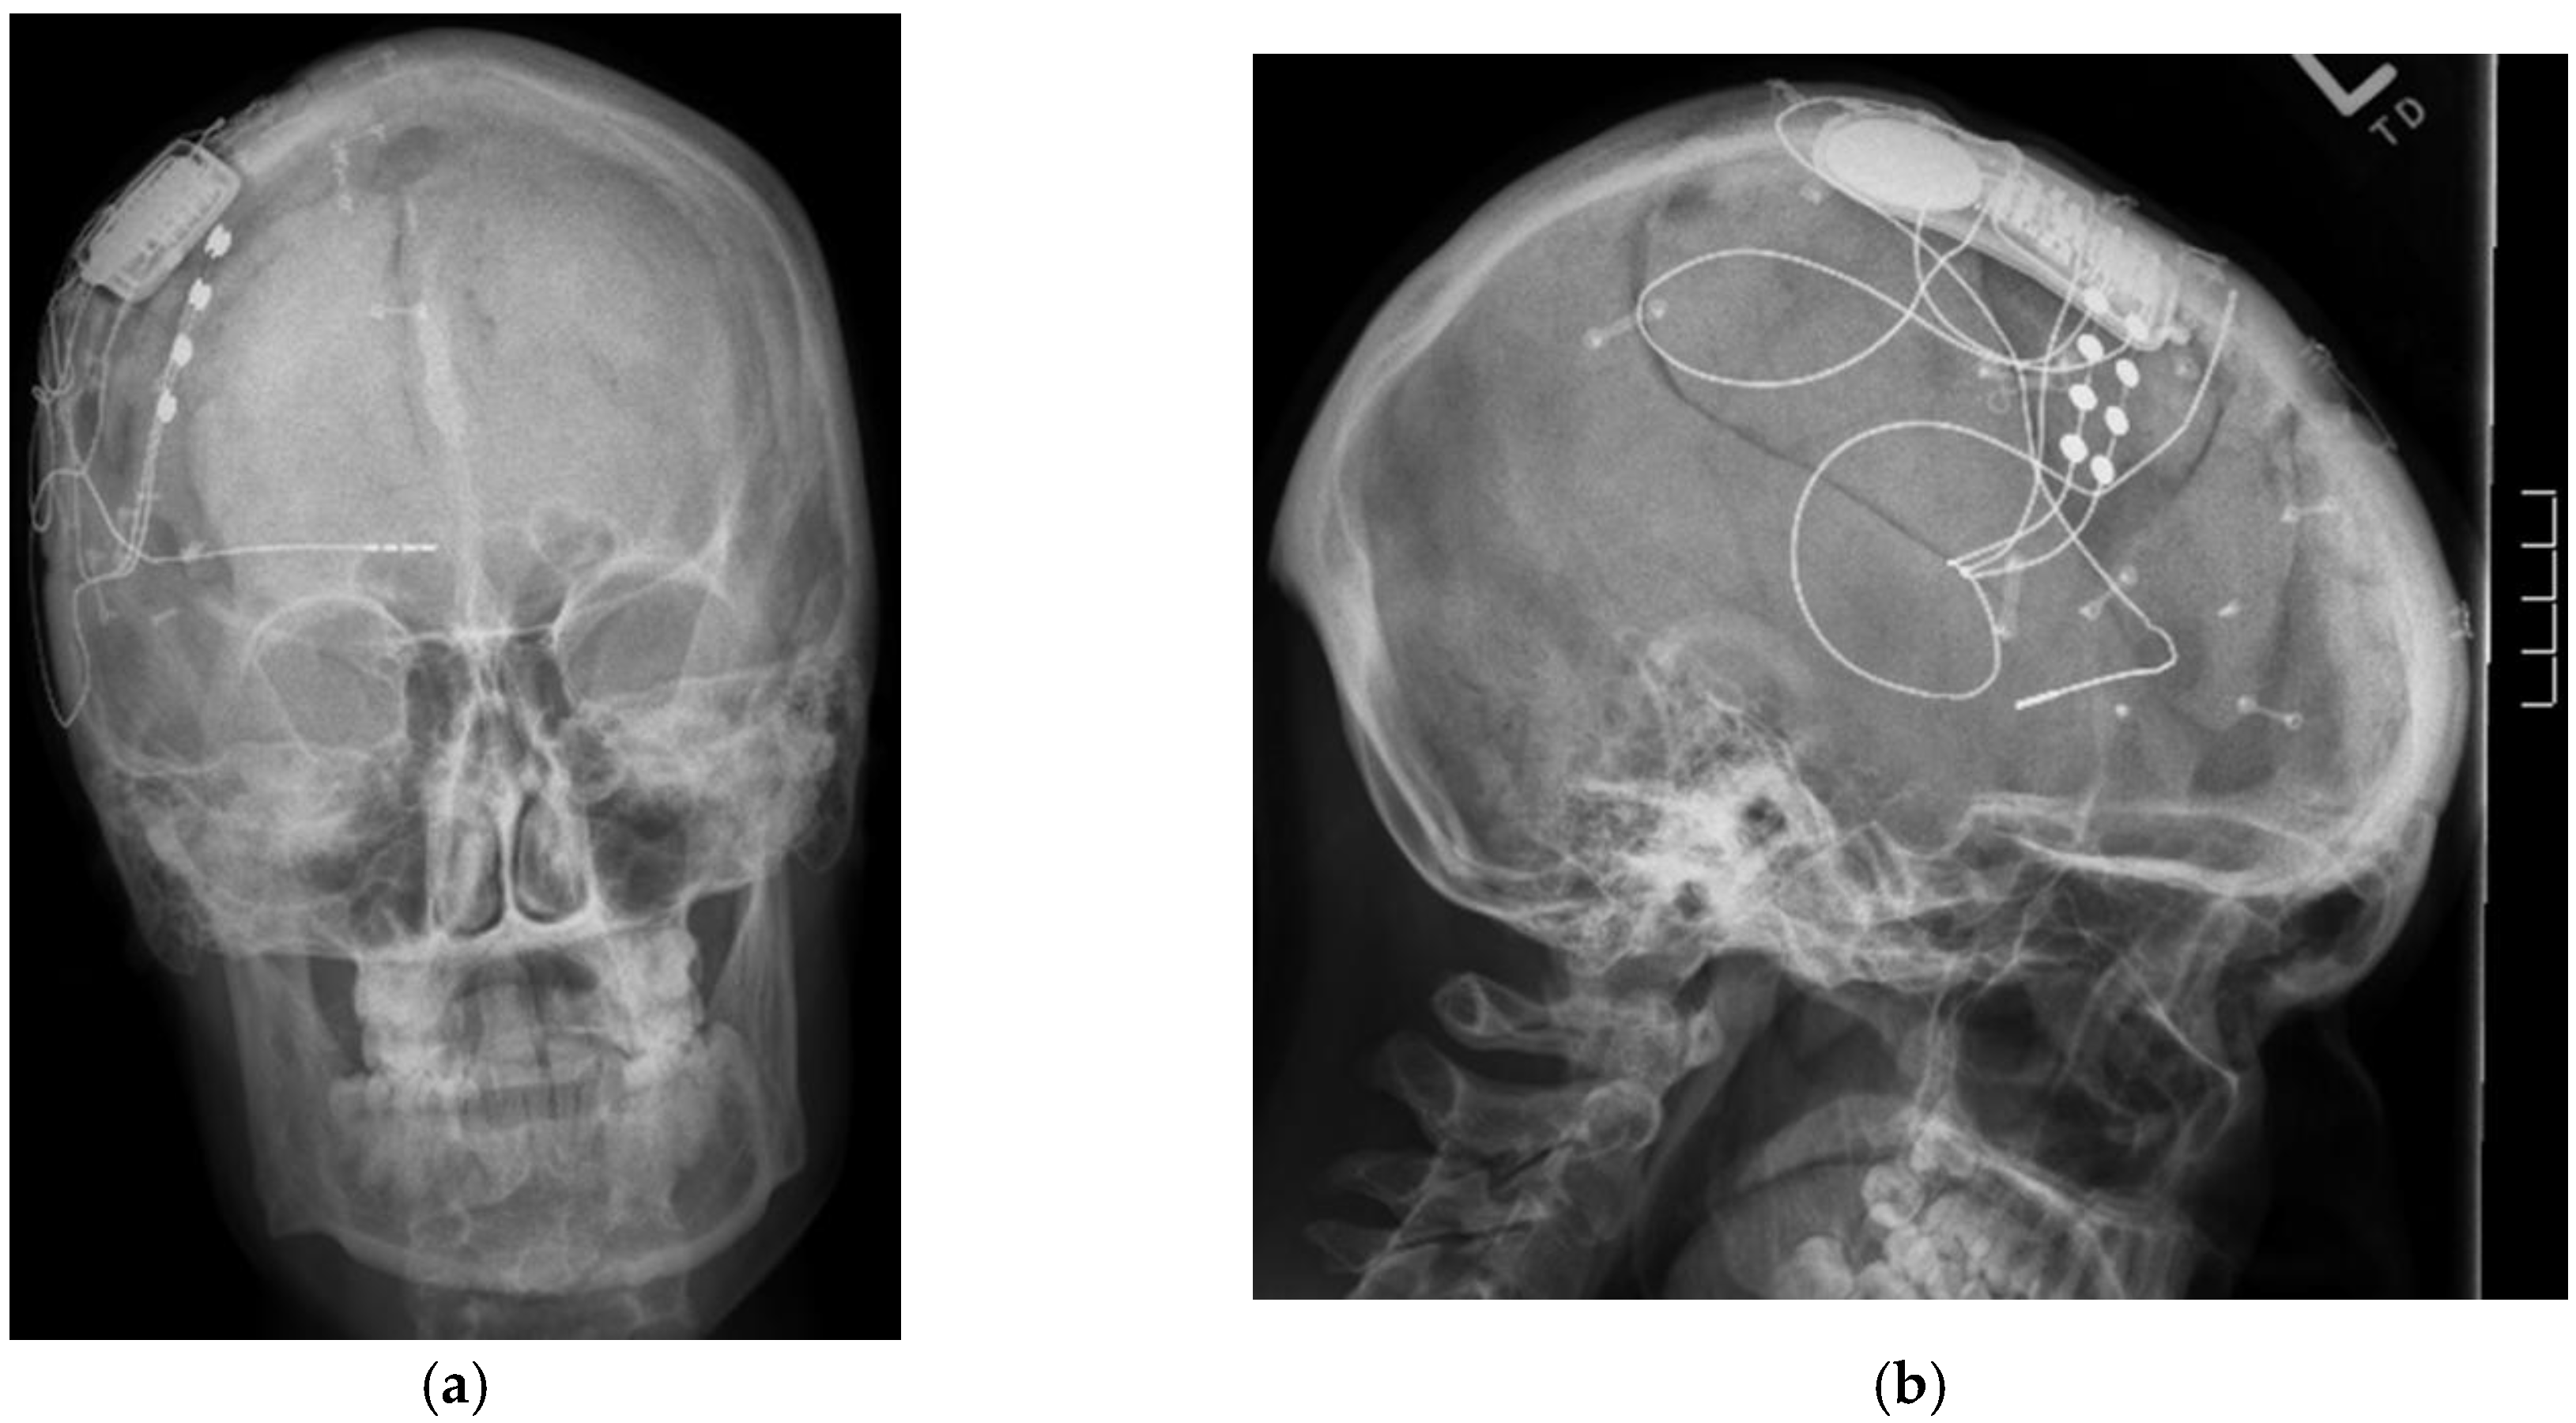

Figure 3.

(a) Antero-posterior skull X-rays of implanted responsive neurostimulation; (b) Lateral skull X-rays of implanted responsive neurostimulation.